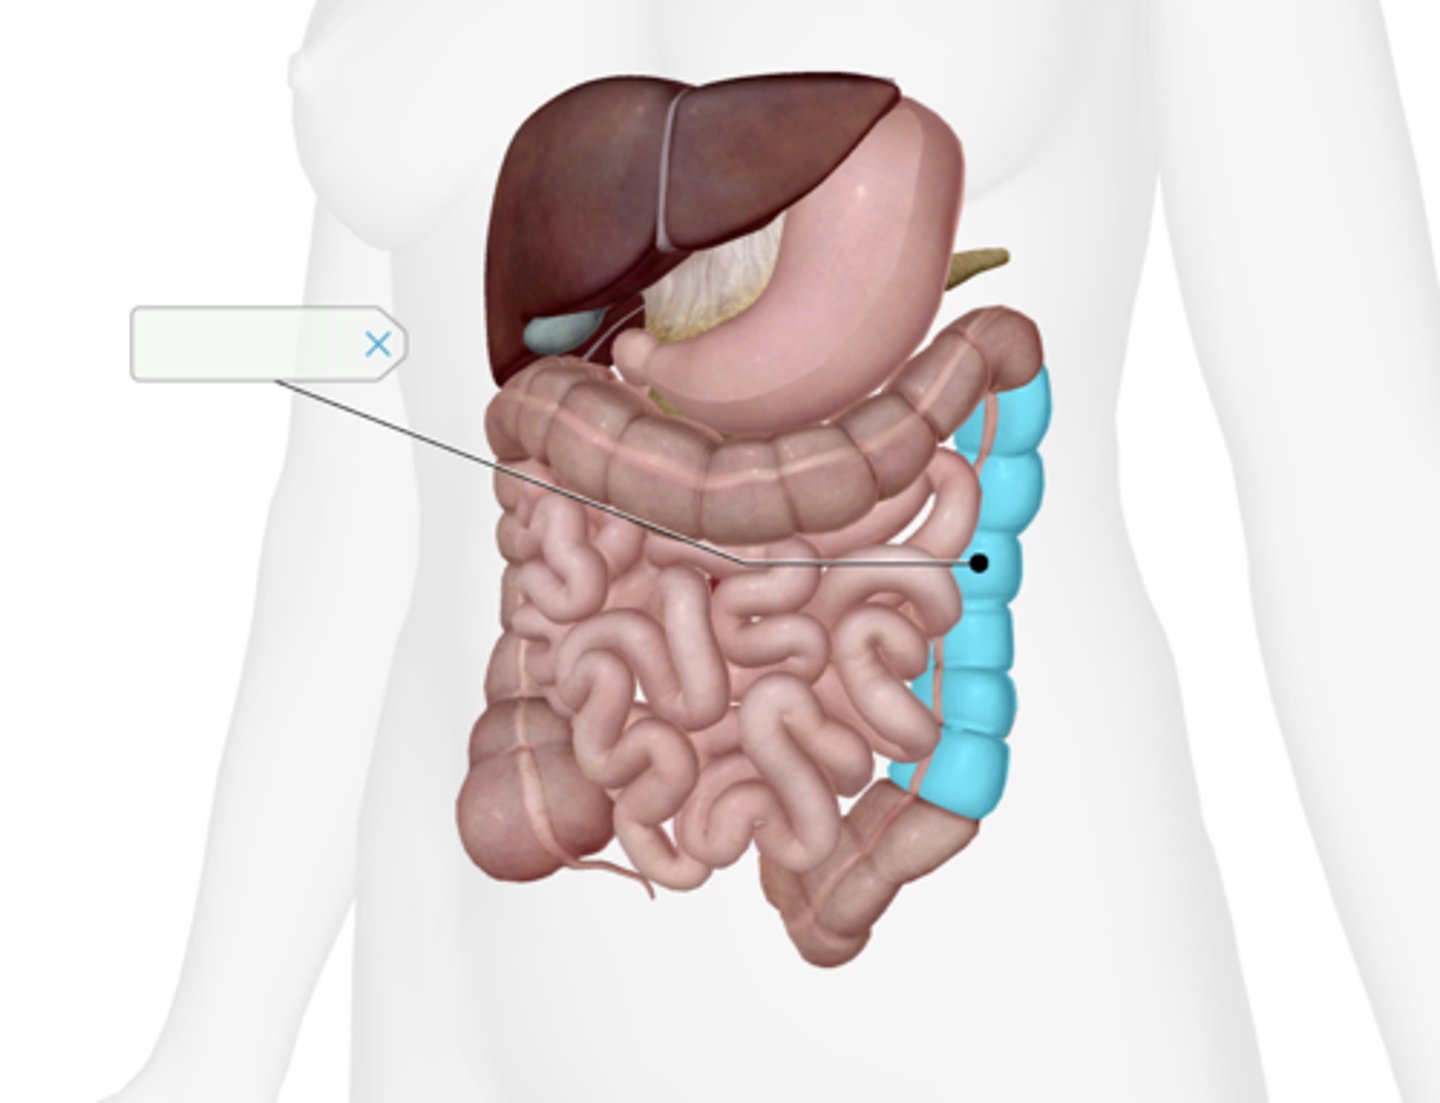

Descending colon